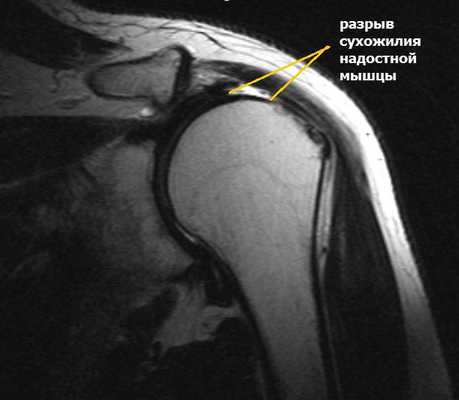

МРТ плечевого сустава. Т2-взвешенная корональная МРТ. Разрыв вращательной манжеты. Цветовая обработка изображения.

Разрыв вращательной манжеты – также характерное повреждение области плеча – может быть связан как с травмой, так и дегенеративными процессами. Разрывы вращательной манжеты бывают полные и неполные. Кроме того, по МРТ плечевого сустава выделяют 3 градации, в основе которых лежит не только изменение сигнала на Т2-зависимых томограммах, но и морфологические изменения сухожилия.

МРТ. Корональная Т2-зависимая томограмма с подавлением сигнала от жира. Полный разрыв сухожилия надостной мышцы.

При МРТ плечевого сустава косвенным признаком разрыва вращательной манжеты служит высокий сигнал на Т2-взвешенных от поверхности сустава до субакромиальной (субдельтовидной) сумки. Частичные разрывы чаще всего по передней поверхности сухожилия м.supraspinatus, реже примыкая к большой бугристости или сухожилия м. infraspinatus.